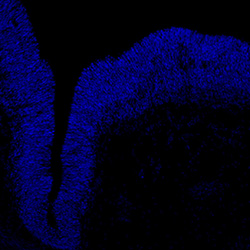

An in vivo and in vitro spatiotemporal profile of human midbrain development

An anatomical analysis of the developing human midbrain from 6 post-conceptional weeks (PCW) to 22 PCW reveals increased tissue complexity, characterized by the emergence of dopaminergic nuclei, as highlighted by immunofluorescence analysis for tyrosine hydroxylase (TH).

DAPI

6PCW human midbrain